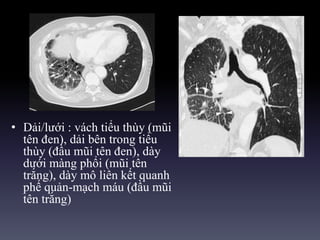

• Dải/lưới : vách tiểu thùy (mũi

tên đen), dải bên trong tiểu

thùy (đầu mũi tên đen), dày

dưới màng phổi (mũi tên

trắng), dày mô liên kết quanh

phế quản-mạch máu (đầu mũi

tên trắng)